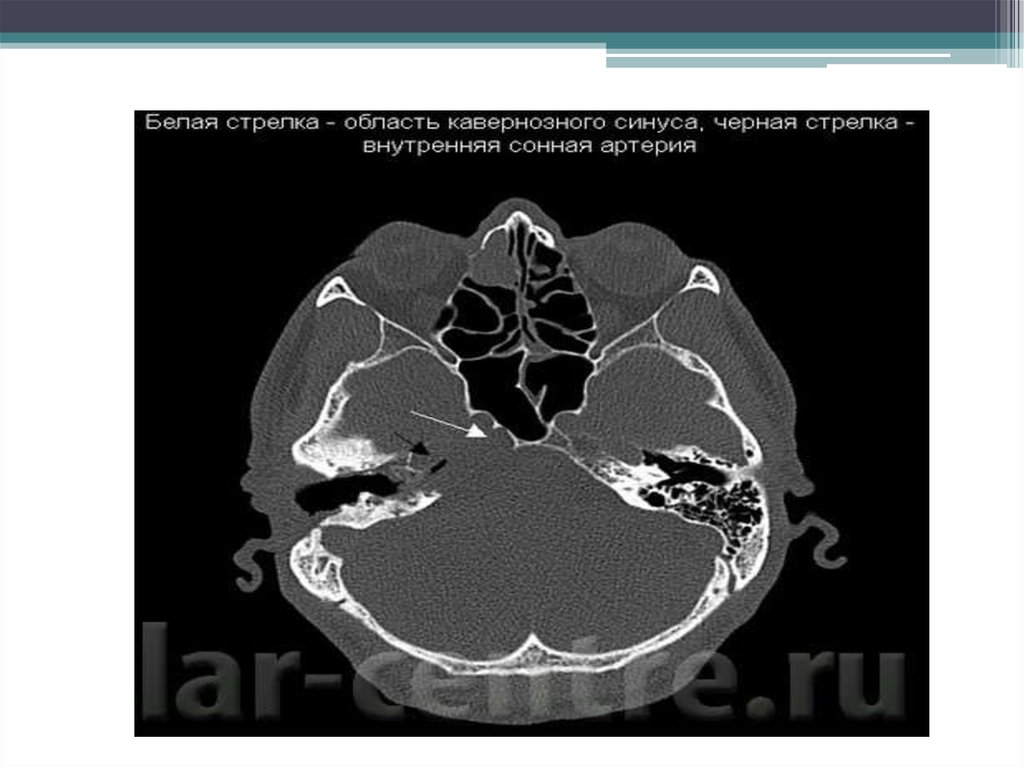

• Менингиома - доброкачественная опухоль

• В отделение нейрохирургии обратилась

пациентка 54 лет с жалобами на

нарастающую головную боль, нарушение

речи. По результатам МРТ исследования с

контрастным усилением выявлена крупная

менингиома левой височной области с массэффектом и компрессией желудочковой

системы. Выполнено оперативное

вмешательство - удаление опухоли с

иссечением и пластикой пораженной твердой

мозговой оболочки (зона исходного роста

опухоли).